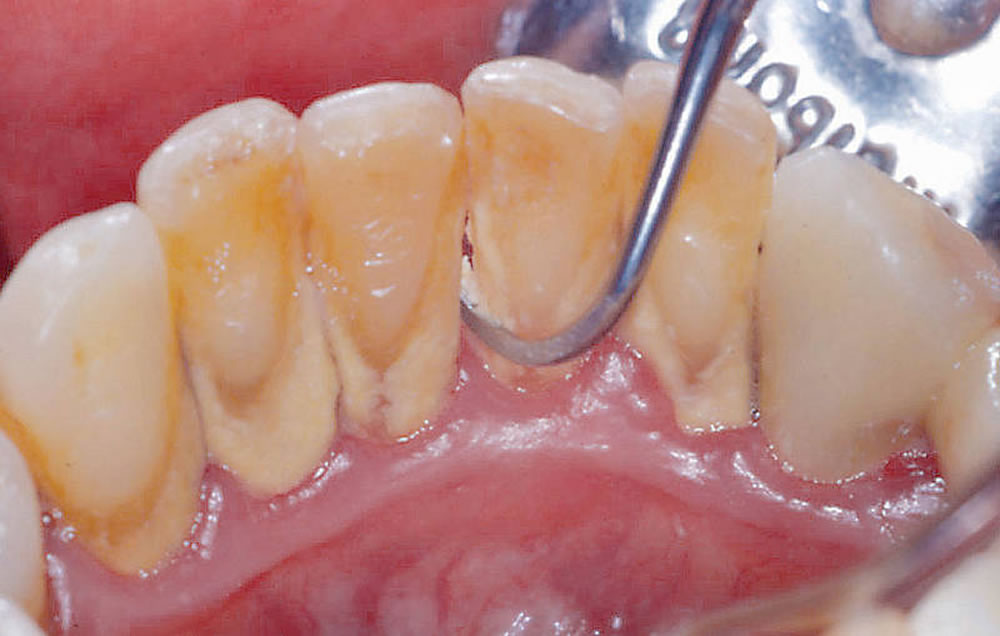

①2つのスケーラーを使用して歯垢・歯石の除去

徳壮会新津田沼歯科クリニックでは歯垢や歯石を取り除くスケーリングの際に、「超音波スケーラー」と「ハンドスケーラー」の2つを使用しています。

それぞれの特徴を活かし、適材適所で使い分けることで、効率的で精度の高い歯垢・歯石の除去を実施しています。

超音波スケーラー

超音波振動によって、頑固な歯石も簡単に取り除く事が出来ます。短時間で広範囲の処置が可能なため、当院では最初に超音波スケーラーを使用して、お口全体の汚れを効率良く取り除きます。

ハンドスケーラー

手動で操作するスケーラーです。処置に時間を要しますが歯と歯の間や歯茎と歯の境目など、細部の歯石除去で力を発揮します。仕上げに使用する事で、取り残しのない精密な処置が可能となります。